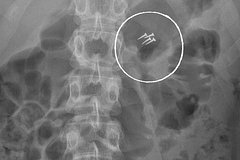

Среди прочего, люди обращались к врачам за помощью из-за проглоченных наушников, украшений. Особо отмечается случай, когда пациент проглотил зажатые в зубах и ненамеренно проглоченные в процессе ремонта гвозди.

«Случаи курьезные, но проблема крайне серьезная — ежегодно в НИИ поступают десятки пациентов с инородными телами. Им требуется экстренная медицинская помощь и зачастую длительное восстановление», — отметили медики.